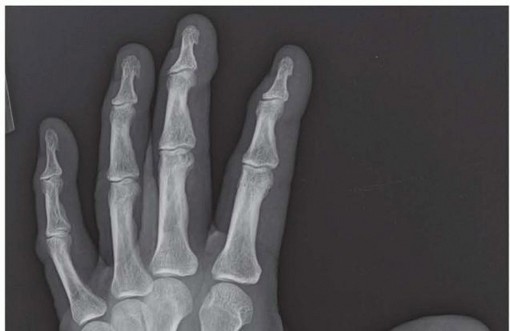

Proximal Interphalangeal and Metacarpophalangeal Joint Silicone Implant Arthroplasty